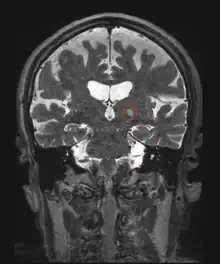

HIFU is combined with other imaging techniques such as medical ultrasound or MRI to enable guidance of the treatment and monitoring.

Neurological disorders

One of the first applications of HIFU was the treatment of Parkinson's disease in the 1940s. Although ineffective at the time, HIFU has the capacity to lesion pathology. A focused ultrasound system is approved in Israel, Canada, Italy, Korea and Russia to treat essential tremor,[6] neuropathic pain,[7] and Parkinsonian tremor.[8] This approach enables treatment of the brain without an incision or radiation. In 2016, the US Food and Drug Administration (FDA) approved Insightec's Exablate system to treat essential tremor.[9] Treatment for other thalamocortical dysrhythmias and psychiatric conditions are under investigation.[10]